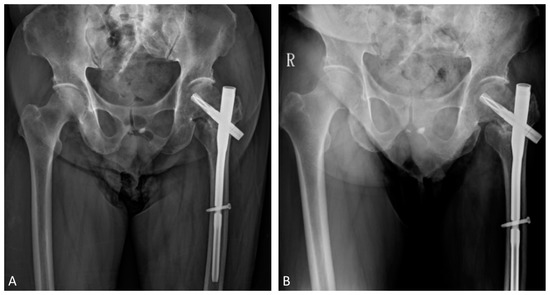

Teriparatide as an Effective Nonsurgical Treatment for a Patient with Basicervical Peritrochanteric Fracture Nonunion—A Case Report

The nonunion rate of surgically treated basicervical peritrochanteric fractures has been reported to be as high as 9%. Due to the high 1-year mortality rate following revision surgery, finding an effective nonsurgical treatment option is of interest. Over the last decade, numerous reports have been published that have suggested teriparatide as an effective treatment for certain types of fracture nonunion. However, the literature focused on teriparatide treatment for proximal femoral fracture nonunion is scanty. A 70-year-old man suffering from a left hip basicervical peritrochanteric fracture received cephalomedullary nail fixation. Nine months after the surgery, the patient still complained of left hip pain referring to the medial thigh with an antalgic limping gait. No sign of healing was noted for more than a consecutive 3 months of follow-up. Fracture nonunion was diagnosed and further confirmed by the computed tomography (CT). The patient preferred nonsurgical treatment after thorough discussion. He then received 4 months of subcutaneous teriparatide injections, 20 mcg daily. After less than 4 months of teriparatide treatment, a follow-up CT confirmed fracture union and the patient’s pain subsided. The patient also tolerated independent ambulation afterward. Teriparatide has been reported to be an effective treatment for certain types of fracture nonunion. Our case goes a step further to expand its possible application for basicervical peritrochanteric fracture nonunion. However, further larger scale studies are needed to confirm its efficacy. Full article

Show Figures

Figure 1